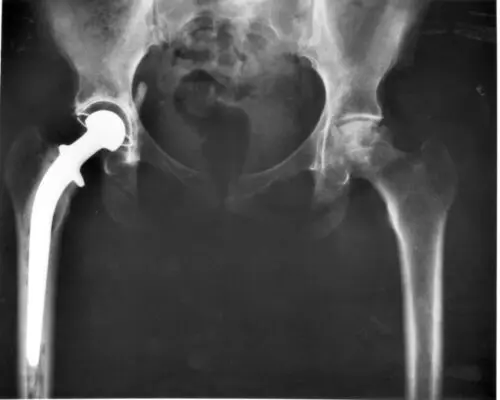

How the MoM Hip Implant Works

The ASR XL Acetabular total hip replacement system consists of three parts: a ball, a stem, and a shell. The shell is what fits inside the hip socket (also called the acetabulum, and where the product gets its name). The stem is fixed inside the femur bone, and the ball is fixed at the top of the stem like the femoral head, fitting into the socket. This design is a departure from previous hip implants, which had four components: the ball, stem, shell, and a lining to cushion the ball from the shell. By getting rid of the lining, DePuy increased the femoral head’s surface area, which made the new hip less likely to dislocate. But it increased the friction between the ball and the shell, both made out of a cobalt-chrome-molybdenum.